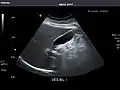

Gallbladder: No stones, wall thickening, or pericholecystic fluid.

Gallbladder